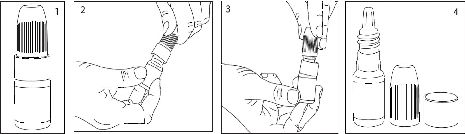

- LATROST-T'nin şişesini alınız.

- Ellerinizi yıkayınız.

- Şişenin kapağını açınız.

- Kapağın altında bulunan halkayı çıkarınız (bkz. Resim 3 ve Resim 4).

- Kapağı halka olmadan tekrar kapatınız. Kapak içerisindeki plastik pin şişenin ucunu delecektir (bkz. Resim 5).

LATROST-T göze aşağıdaki şekilde uygulanır.

1. Parmağınızın uç bölümünü kullanarak, hasta gözünüzün alt göz kapağını aşağıya doğru yavaşça çekiniz.

2. Damlatıcmm ucunu gözünüze yaklaştırınız ancak gözünüze değdirmeyiniz.

3. Damlatıcıyı yavaşça sıkınız ve gözünüze sadece bir damla damlatınız. Daha soma göz kapağını serbest bırakınız.

4. LATROST-T kullanımından soma, parmağınız ile gözünüzün kenarmdan burnunuza doğru aşağıdaki şekilde gibi 2 dakika bastırınız. Bu latanoprost ve timololün

vücudunuzun diğer bölümlerine geçişini engellemeye yardımcı olacaktır.

5. Doktorunuz diğer gözünüze de uygulamanızı söyledi ise, ona da aynı şekilde uygulama yapınız.

6. Şişeyi kapatınız.